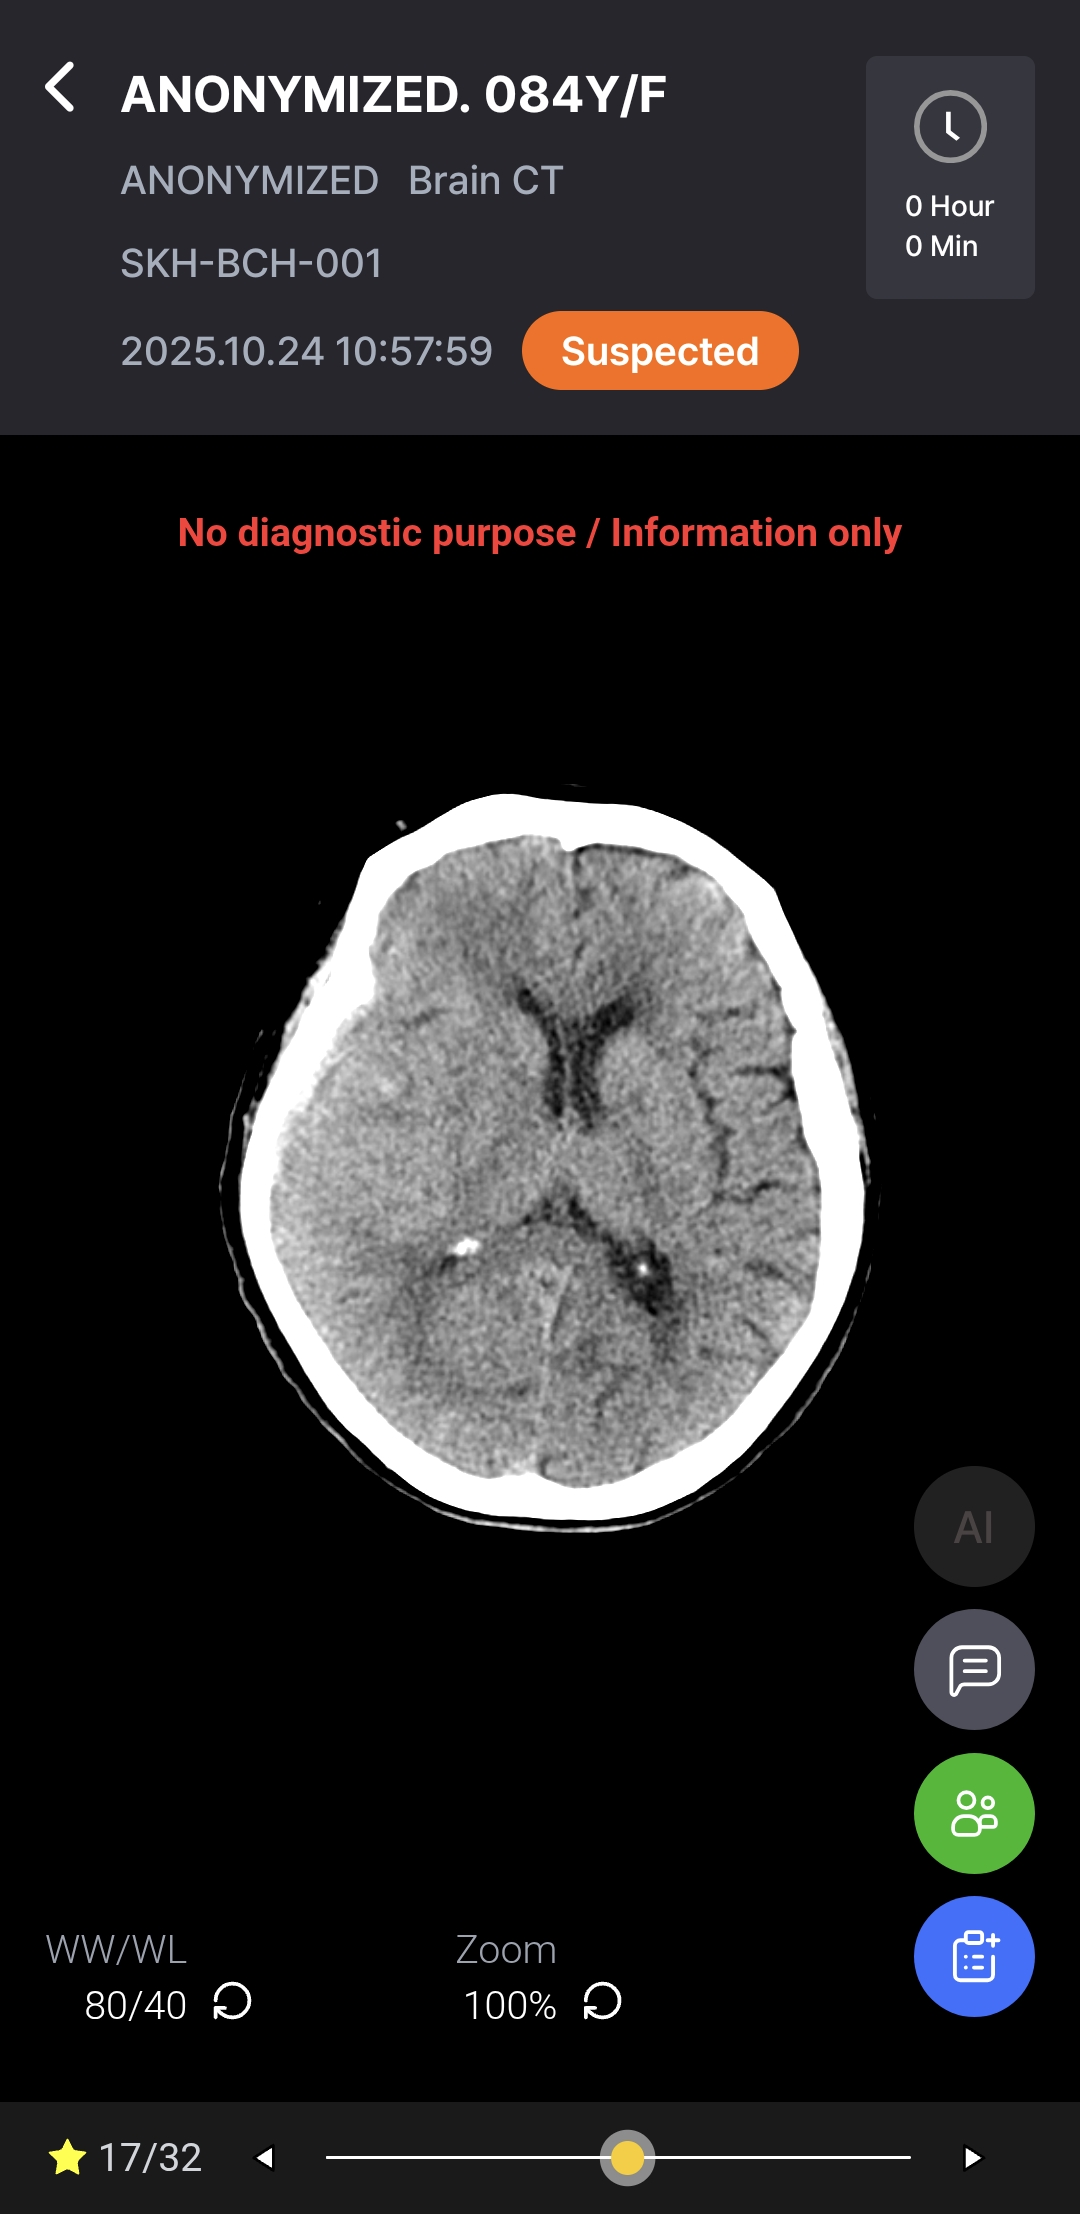

AI-powered diagnostic support for rapid, accurate detection and localization of brain hemorrhages on non-contrast CT, with ROI visualization and volume quantification to help radiologists assess hemorrhagic regions.

As a Radiological Computer Aided Triage And Notification Software, Hyper Insight™ – ICH functions as a triage and notification tool – supporting, not replacing, medical judgment. Final diagnosis and treatment decisions remain the responsibility of qualified medical professionals.